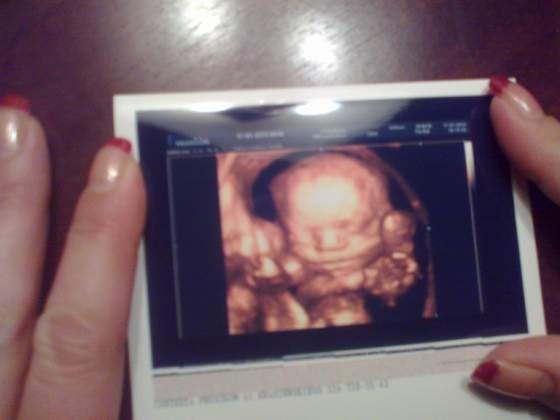

ale mam zdjęcie:-)